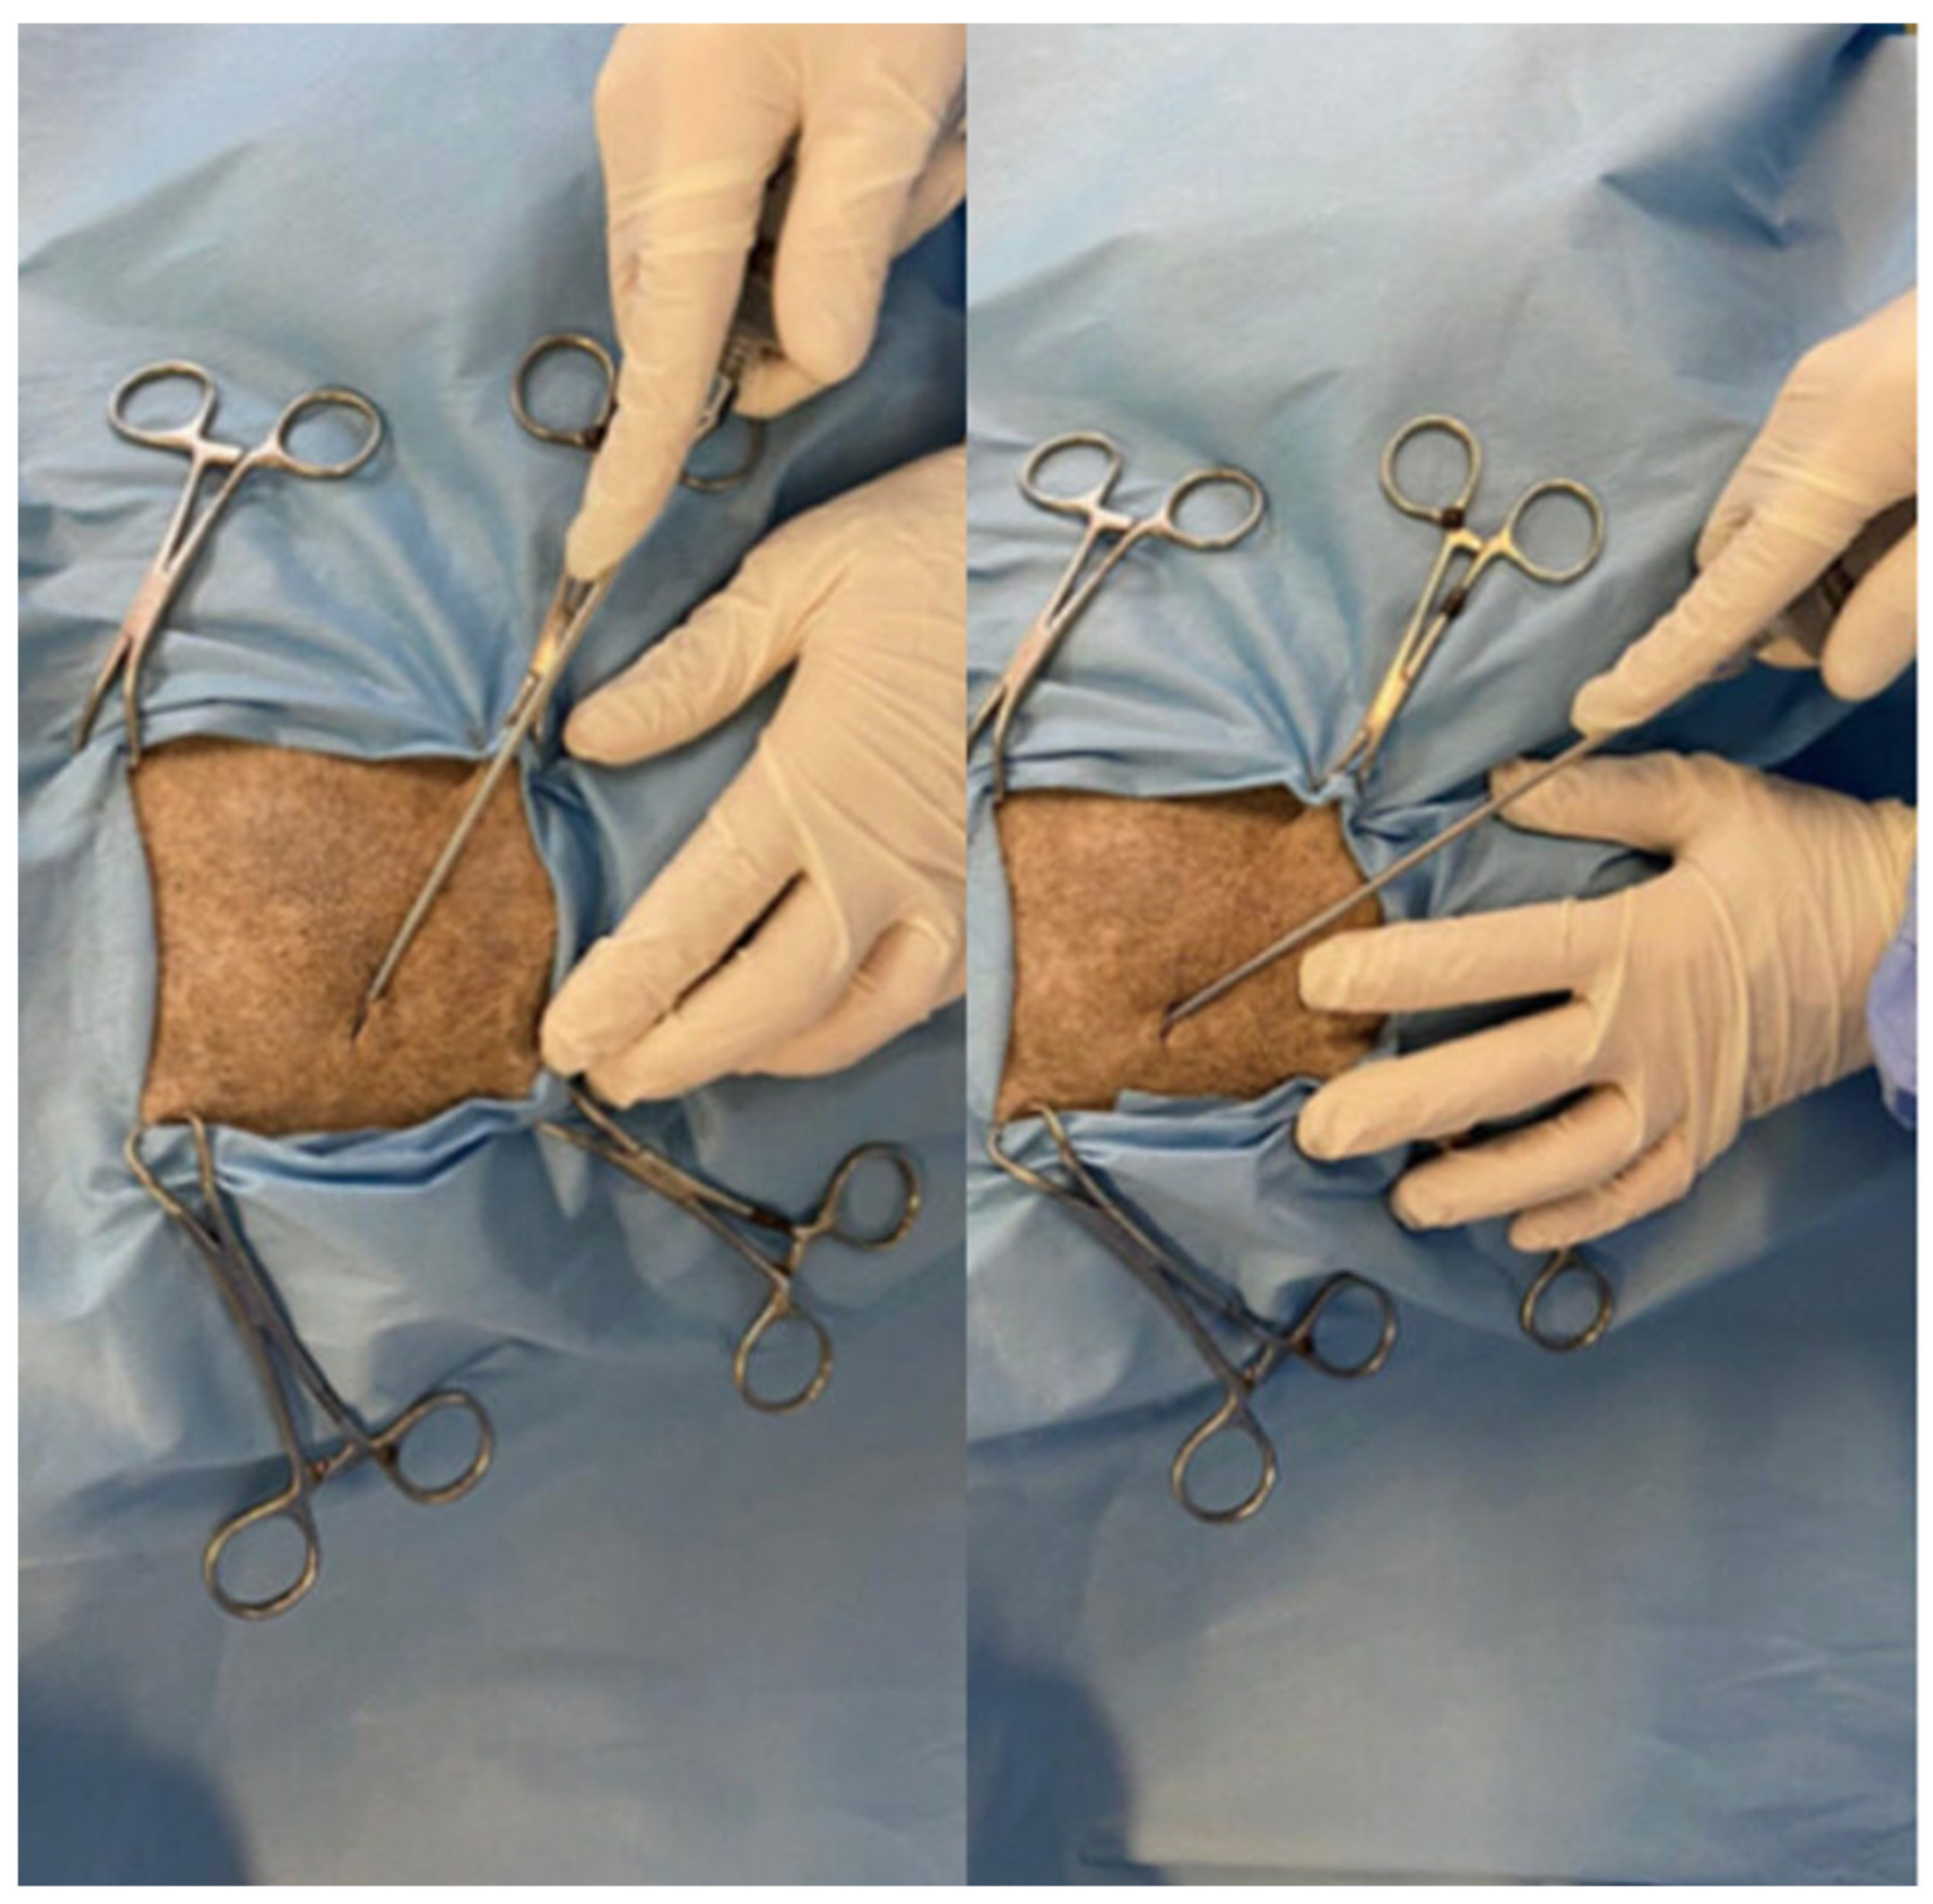

2.6. Study Group Therapy (MFAT Group)